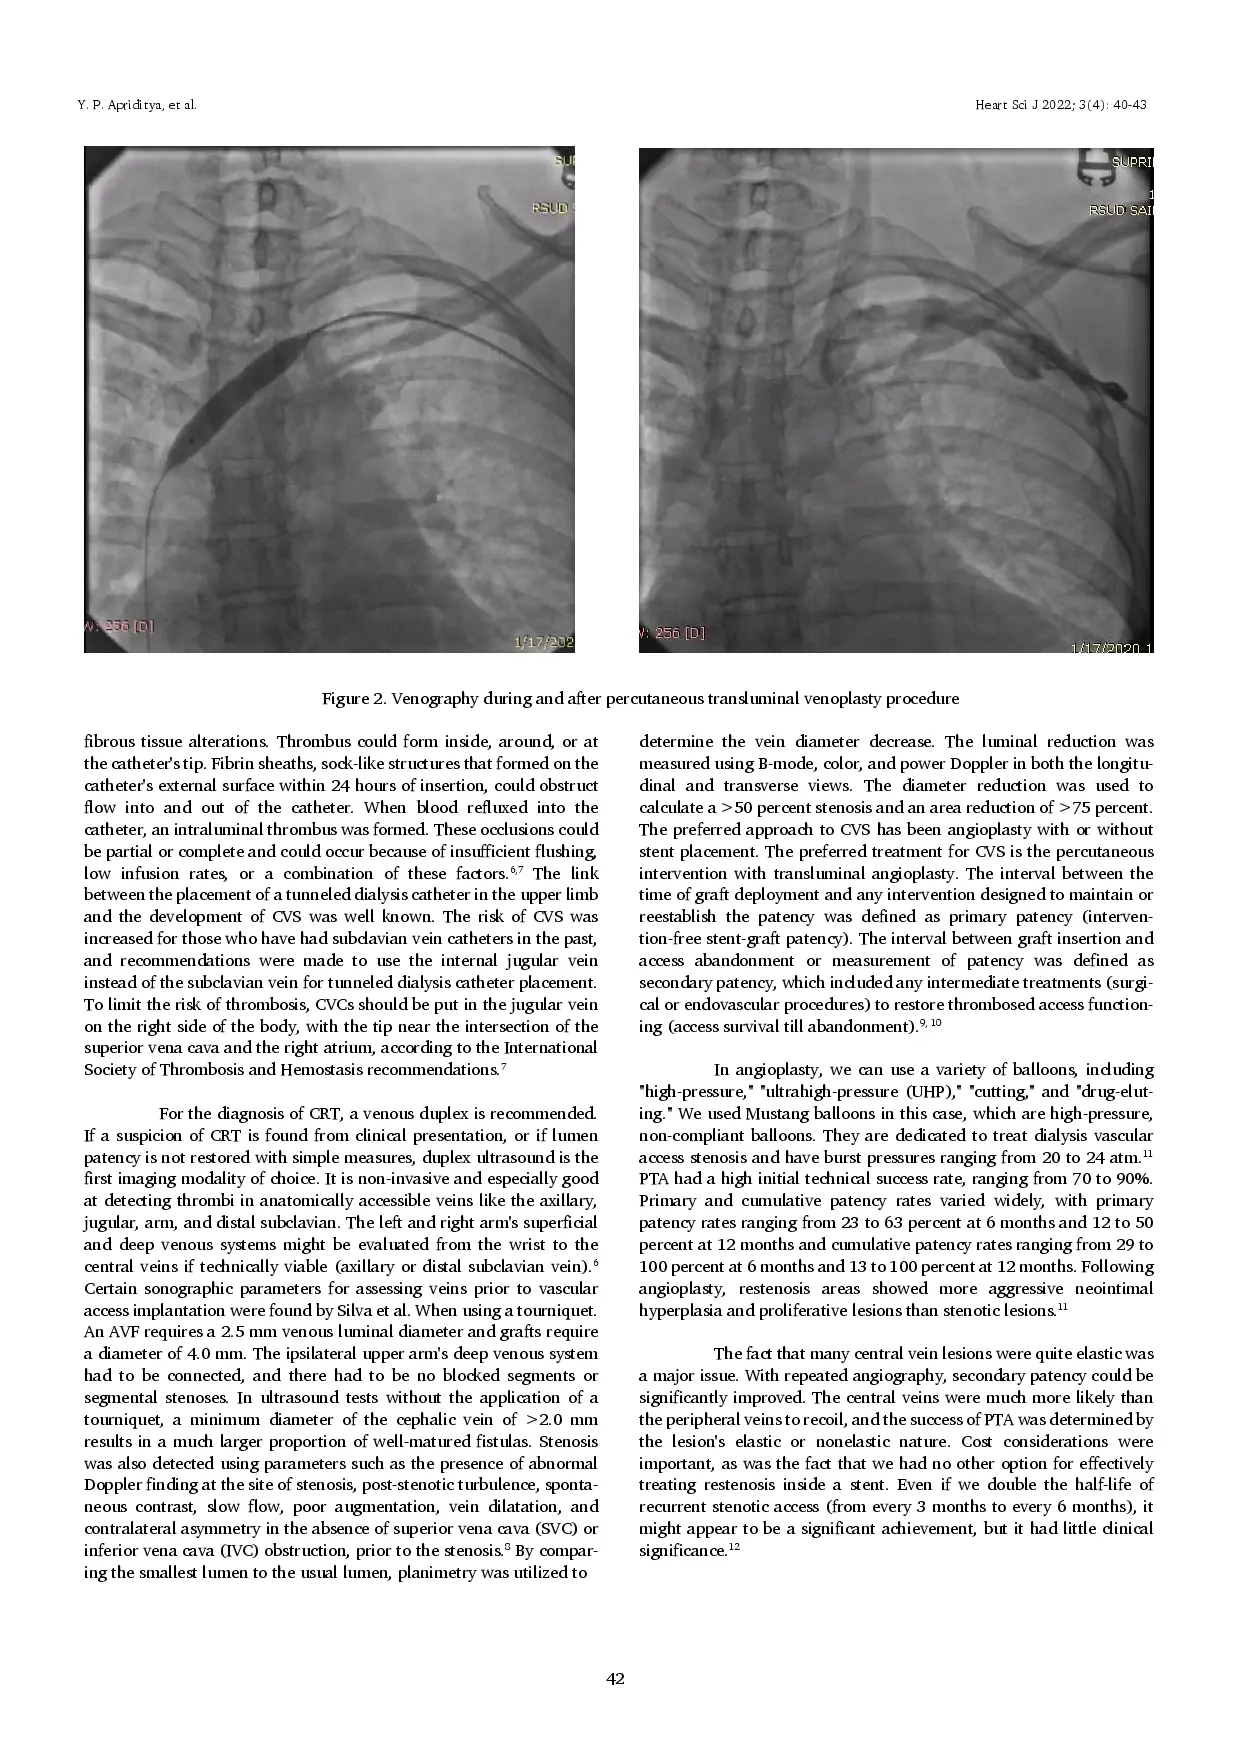

Kateter hemodialisis masih menjadi pilihan yang layak bagi banyak pasien penyakit ginjal kronis (CKD).Selain infeksi terkait kateter, perkembangan CRS bertanggung jawab atas sebagian besar malfungsi kateter.Reaksi dinding vena terhadap kateter dan trombus yang ditimbulkannya bersifat dinamis dan terus-menerus.Angioplasti transluminal perkutan (PTA) merupakan pengobatan yang relatif aman dan efektif untuk CVS, dengan tingkat keberhasilan tinggi, efek samping minimal, dan hasil radiologis serta klinis yang baik.